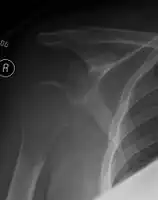

1.a. X-ray: solitary plasmacytoma upper arm near shoulder -

1.b. CT scan: solitary plasmacytoma upper arm near shoulder -